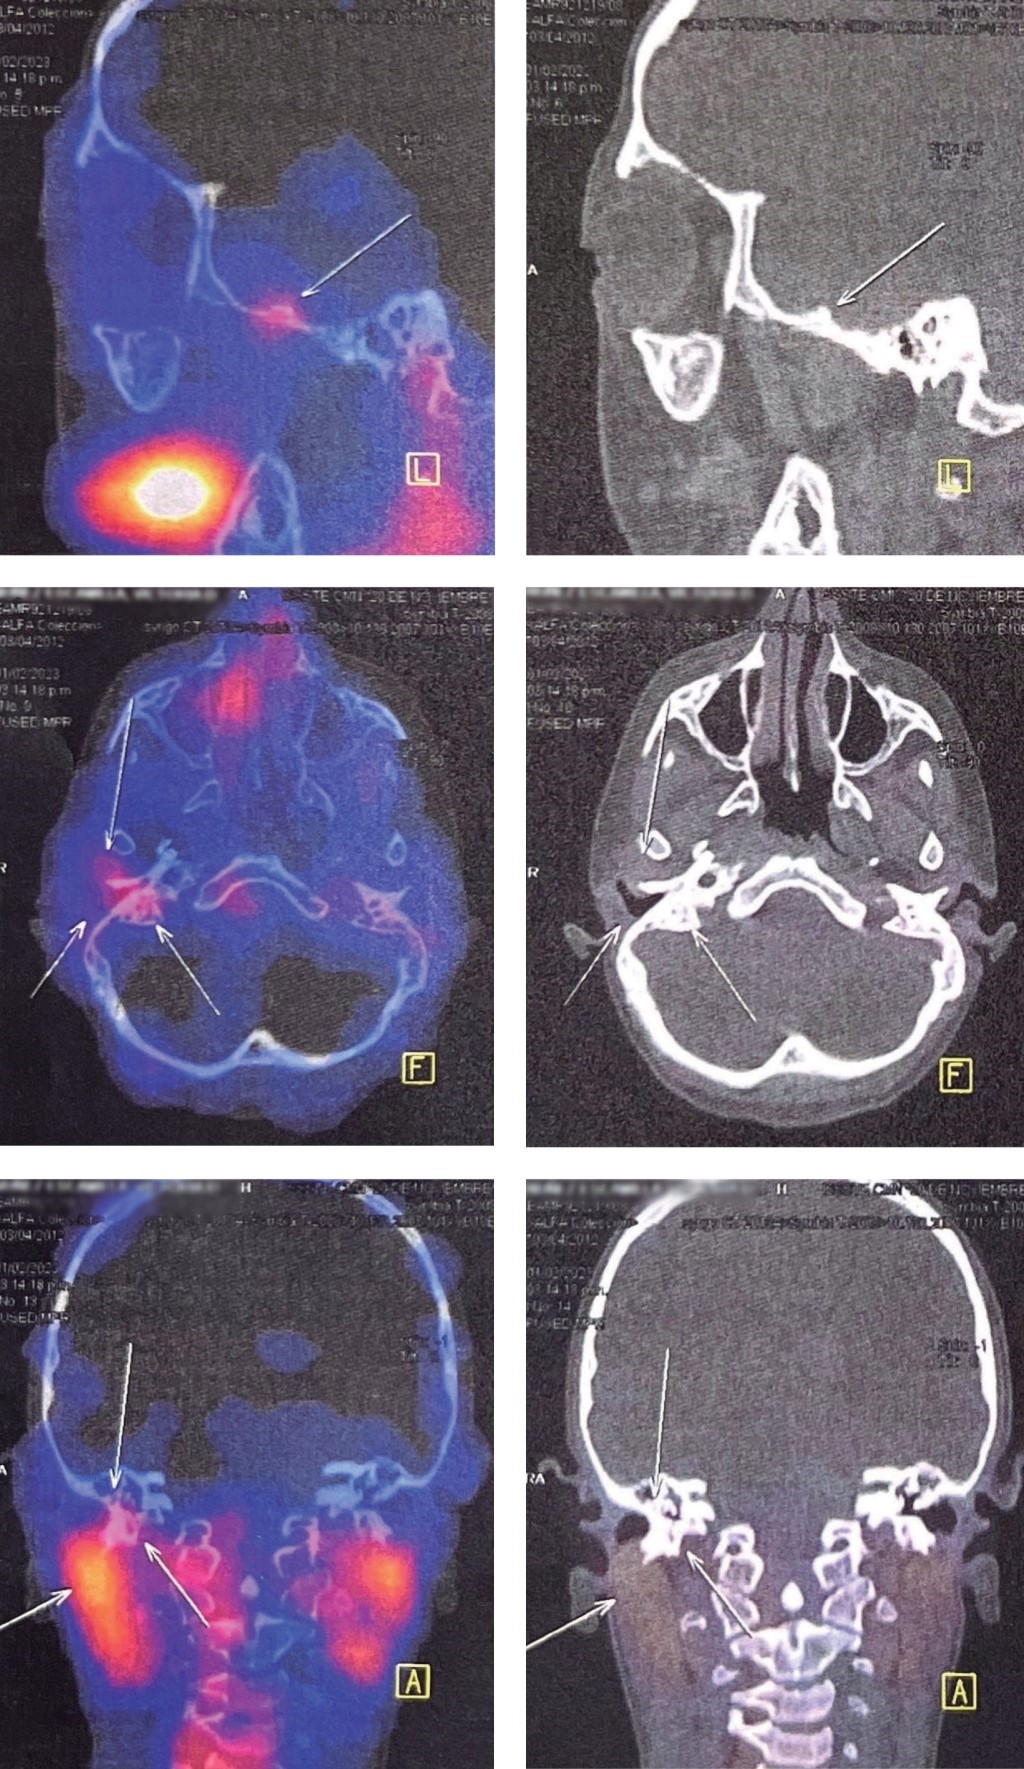

Temporoparietal fascial flap for radical mastoidectomy defect obliteration in a pediatric patient in a national reference center

Rivas-Jiménez J, Mejía-Solís EA, Rojas-Gutiérrez CD, Haro-Cruz JS, Tejada-Aldazosa JE

temporoparietal fascia flap, radical mastoidectomy, pediatric craniofacial reconstruction.

The temporoparietal fascia flap is one of the most versatile flaps for reconstruction of complex head and neck defects; even though its description in cases of mastoidectomy in the pediatric population and its outcomes are not reported in the literature. We present the case of a 10-year-old patient with chronic otitis media who underwent radical mastoidectomy with subsequent reconstruction by temporoparietal fascia flap with a good result. The temporoparietal fascia flap is a flap that can be used in cases of osteomyelitis in the temporal region offering an appropriate coverage of the region with minimal donor site morbidity and favorable results.

Figure 1

Figure 2

Figure 3

Figure 4

Figure 5

Figure 6